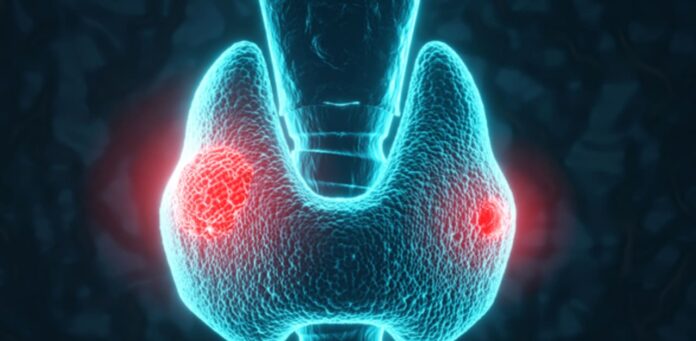

Six FDA-cleared AI platforms are enhancing ultrasound evaluations for thyroid nodules, demonstrating improved diagnostic accuracy over inexperienced physicians, according to a review by Dr. Johnson Thomas and Dr. Franklin N. Tessler published in Thyroid. These platforms utilize established risk stratification systems, such as ACR TI-RADS, to analyze sonograms and estimate malignancy risks. Notable systems include AmCAD-UT, which notably increased accuracy among junior readers, and S-Detect, which achieved 95% sensitivity in its evaluations. Although multimodal large language models like ChatGPT-4o showed weaker performance in diagnostic tasks, ongoing research is investigating AI for lymph node and cytology assessments. Despite promising capabilities, barriers such as workflow friction and reimbursement issues hinder widespread adoption. Experts emphasize the need for independent validation and tailored implementation strategies to integrate AI effectively into clinical environments. Overall, while AI offers potential enhancements for thyroid nodule assessments, careful selection and integration into existing workflows are crucial for optimal performance.